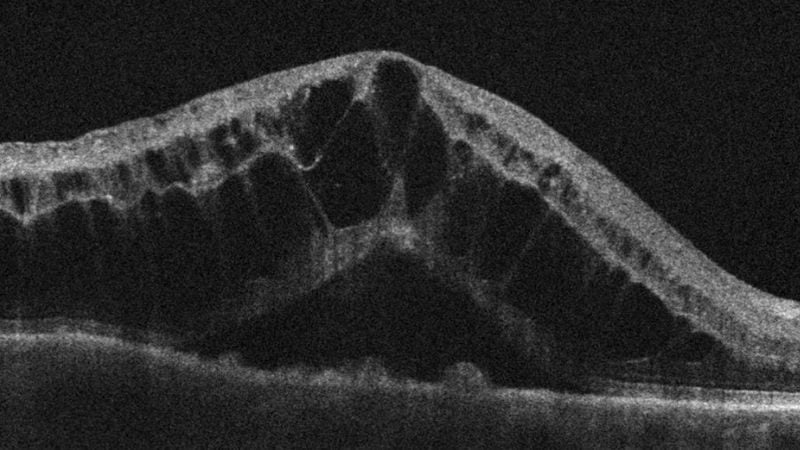

Hình ảnh OCT cho thấy phù hoàng điểm dạng nang. (Nguồn: Internet)

OCT bán phần sau tái hiện chi tiết các lớp võng mạc, từ lớp biểu mô sắc tố đến màng giới hạn trong. Nhờ đó, bác sĩ có thể đánh giá độ dày hoàng điểm, phát hiện phù, dịch dưới võng mạc, màng trước võng mạc hoặc lỗ hoàng điểm. Kỹ thuật này đặc biệt quan trọng trong bệnh võng mạc tiểu đường và thoái hóa hoàng điểm tuổi già, vì OCT giúp phát hiện tổn thương từ giai đoạn rất sớm. Đối với glaucoma, OCT cung cấp thông tin về độ dày lớp sợi thần kinh quanh gai thị – yếu tố then chốt trong việc theo dõi tiến triển bệnh.